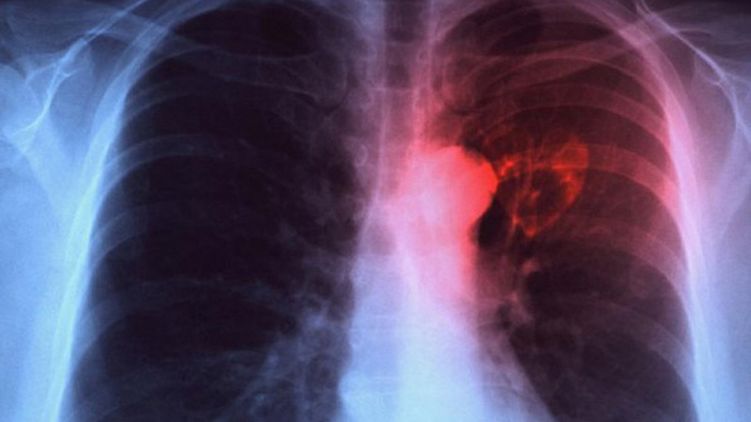

Минздрав предрек Украине вспышку туберкулеза через два-три года. Фото: Flickr

Если сложная ситуация с финансированием медучереждений не изменится в ближайшее время в Украине случится вспышка туберкулеза. Дефицит бюджета противотуберкулезных больниц доходит до 80%.

"На сегодня у нас дефицит финансирования противотуберкулезных учреждений доходит до 80%. Последствия будут таковы: за два-три года получим рост заболеваемости на 30%, рост смертности и сокращение медработников, которое будет насчитывать тысячи людей", - сказал чиновник.

Напомним, что за первые два месяца 2020 года от туберкулеза в Украине умер 581 человек.